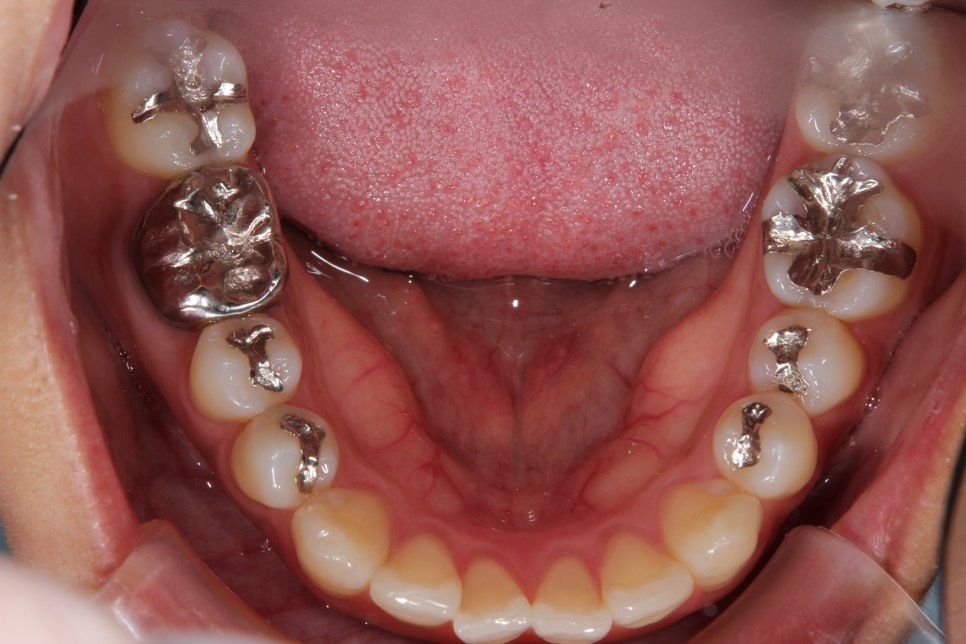

左右のダイレクトボンディング

費用5万円×4本

リスクとして欠ける可能性がある(修復可能)。